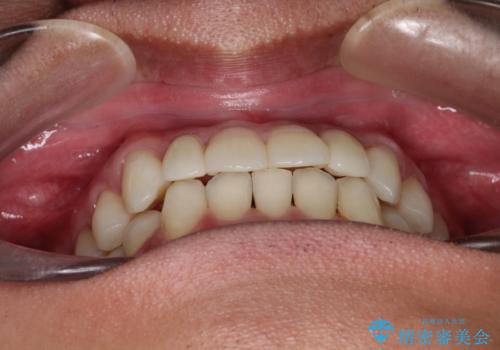

- 前歯のがたつきが気になるとのことで来院されました。

骨格的なところと、上下の歯の大きさのことを考慮して、下の前歯を1本抜歯し、インビザラインにて矯正治療することとなりました。

上の前から2番目の歯がもともと小さかったため、最後にかぶせ物を装着することで、自然な仕上がりにできました。